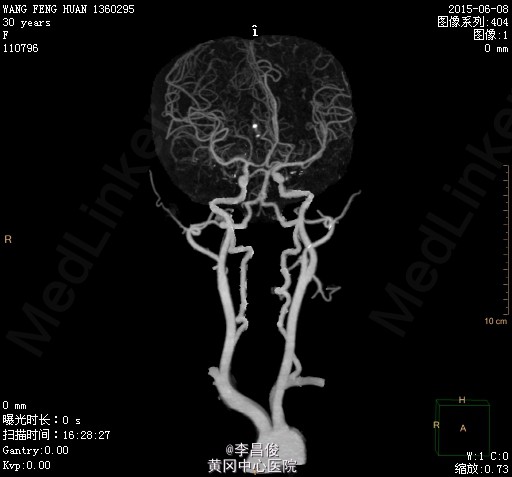

孕期血压基本正常,产后出现的症状是否是存在脑血管畸形?

不好意思,病例中不小心写错了一个地方:出院前检查的是MRA,无明显异常。